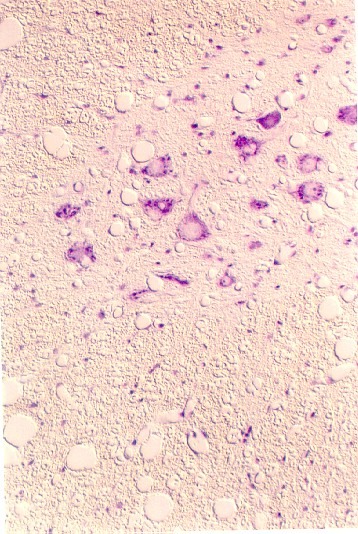

The next photographs illustrate motor neuronal cell bodies at higher magnification. Also, there are small capillaries in the field lined by a single endothelial cell (simple squamous epithelium). Compare these fields with an electron micrograph of a neuronal cell body. In this light microscopic view, the dark purple patches in the cytoplasm are called Nissl bodies. The nucleus is clear.

What is being stained by the Nissl stain?

Dendrites contain Nissl bodies, but axons do not. Can you find both dendritic and axonal processes in either of these fields? Label them.